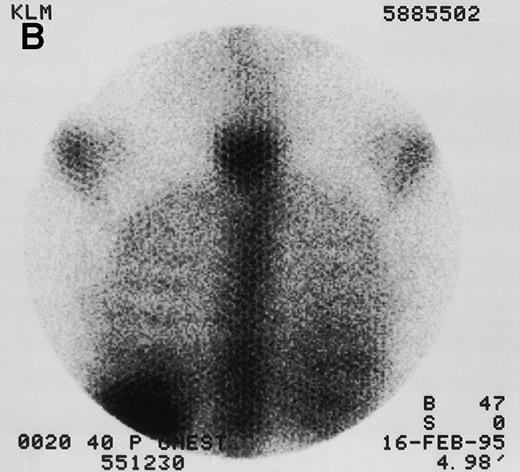

Quantitative gamma images were collected with a dedicated GE 400 AT large-field-of-view camera (General Electric Medical Systems, Milwaukee, WI) with a high energy collimator at hour 0 (end of infusion) and then daily for 2 to 3 days (Fig 1). Regions of interest (spleen, liver, lungs, kidneys if visible, and at least 2 marrow sites) were imaged using a 180° opposing view quantitative planar technique.40 Results were compared with an 131I imaging standard for quantitation and were corrected for whole-body thickness attenuation and radioactive decay. The time-activity curves for each source organ were integrated to obtain residence times. Because organ dose is roughly inversely proportional to mass, corrections were made for patient weight and organ mass when actual weights were known from CT or MRI. This correction was made by multiplying the observed source-organ residence time by the ratio of the defined reference man or woman organ mass to the known organ mass. Radiation absorbed doses were then estimated using methods consistent with those recommended by the Society of Nuclear Medicine’s special committee on Medical Internal Radiation Dose,41,42as previously described.43 The marrow clearance curve was scaled by correcting the biopsy-determined % ID/g of131I-BC8 by a multiplication factor of 2, because antibody cannot bind to the trabecular bone and fat that make up approximately half of the total biopsy weight.44,45 For dosimetry purposes, patient marrow volumes were normalized to the MIRD model values of 1,120 grams for an adult male and 1,050 grams for an adult female. For consistency, the same S values42 were used for all marrow dose calculations throughout the study. Statistical comparisons between disease type or stage and between anti-CD45 and control anti-iodiotype antibody used the Student’s t-test (SPSS for Windows 8.0; SPSS Inc, Chicago, IL).

131I-anti-CD45 antibody localization. Posterior 131I-BC8 images of patient with AML in relapse (UPN 9013) immediately after trace-labeled antibody infusion (A and C) and 40 hours after infusion (B and D). Accumulation of labeled antibody is shown in the ribs, vertebral column, ilium, pelvis, and sacrum, all marrow-rich regions of the axial skeleton.